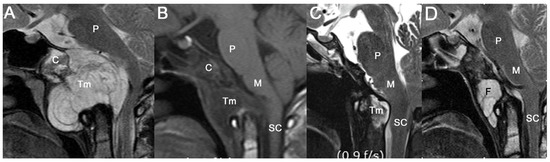

3.1. Tumor Locations and Invasion of Critical Structures

3.3.3. Progression-Free Survival Based on a Remnant Brainstem Lesion